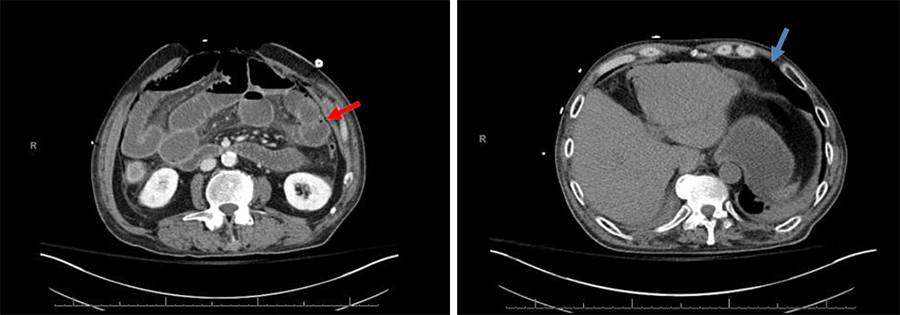

On postoperative day (POD) 3, he developed tachycardia with continued abdominal pain and distension, a normal white blood count, elevated lactate (8.2 mmol/L), and normal levels of phosphorous, magnesium, and potassium, which ruled out a diagnosis of refeeding syndrome, which is a potentially fatal condition that results from rapid fluid and electrolyte shifts that occur in malnourished patients receiving artificial nutrients.1 A computed tomography (CT) scan of the abdomen showed diffuse pneumatosis along with portal venous gas with intraabdominal free air concerning for intestinal ischemia and perforation (Figure 1).

Figure 1. CT Abdomen/Pelvis Without Contrast. Published with Permission

Images show pneumatosis intestinalis (red arrow), free air (blue arrows), and portal venous gas (green arrow).